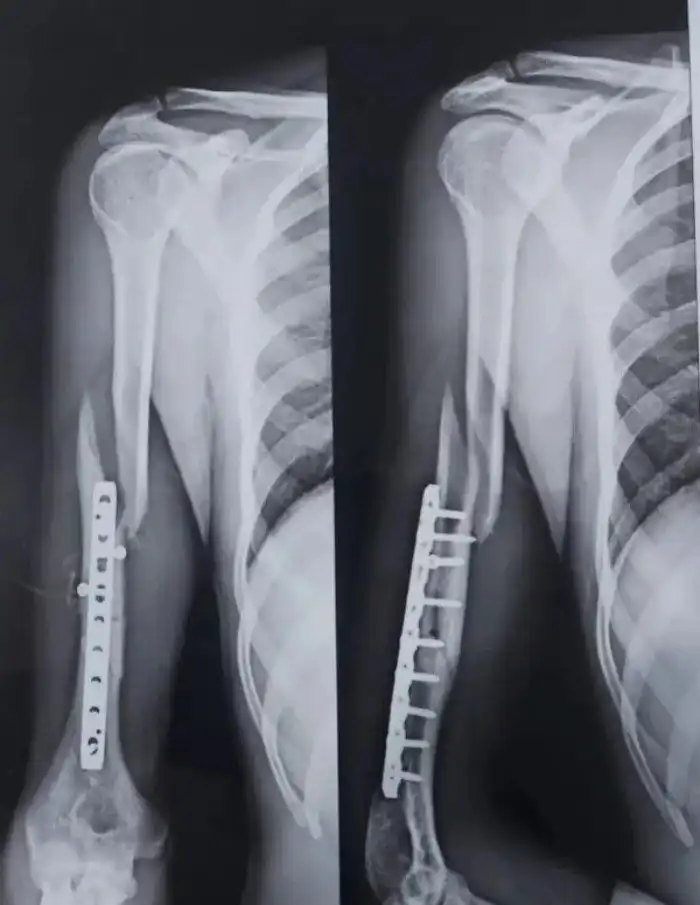

«Мой друг сломал руку во время армрестлинга три месяца назад. Буквально вчера он снова сломал ее, играя в теннис»